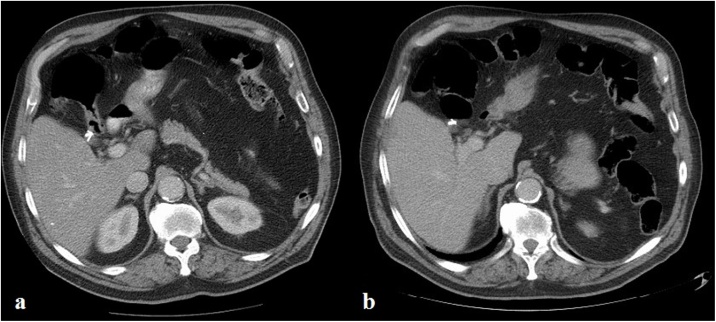

An 82-year-old male patient presented with two-day history of nausea and severe upper abdominal pain, which was deteriorating over several hours. Despite opioid analgesia, his pain was not adequately controlled. He denied any other symptoms pertaining to intestinal or urological organ systems. His medical history was notable for appendicectomy, ischemic heart disease, and hypertension for which he was on anti-hypertensive medications. The patient also had uneventful interval laparoscopic cholecystectomy 22 years earlier, which was performed by a surgeon who was in his learning curve for laparoscopy at the time. During the procedure, three endoclips were used to ligate the cystic duct. He was living with his family and there was no family history of similar condition. Abdominal examination showed severe epigastric and right hypochondrial tenderness. Laboratory tests disclosed a mildly raised alanine aminotransferase (ALT) of 115 U/L (N: 8–41 U/L) and CRP of 15.6 mg/L (N: 0–5 mg/L), but otherwise were normal. A computed tomographic (CT) scan of the abdomen demonstrated a moderately dilated CBD (9 mm), containing a new metallic density when compared to a previous CT scan 14 months earlier (Fig. 1), whereas the number of surgical endoclips at the hepatic hilum has decreased from three to two (Fig. 2a, b). A clinical diagnosis of endoclip migration into the CBD was entertained.